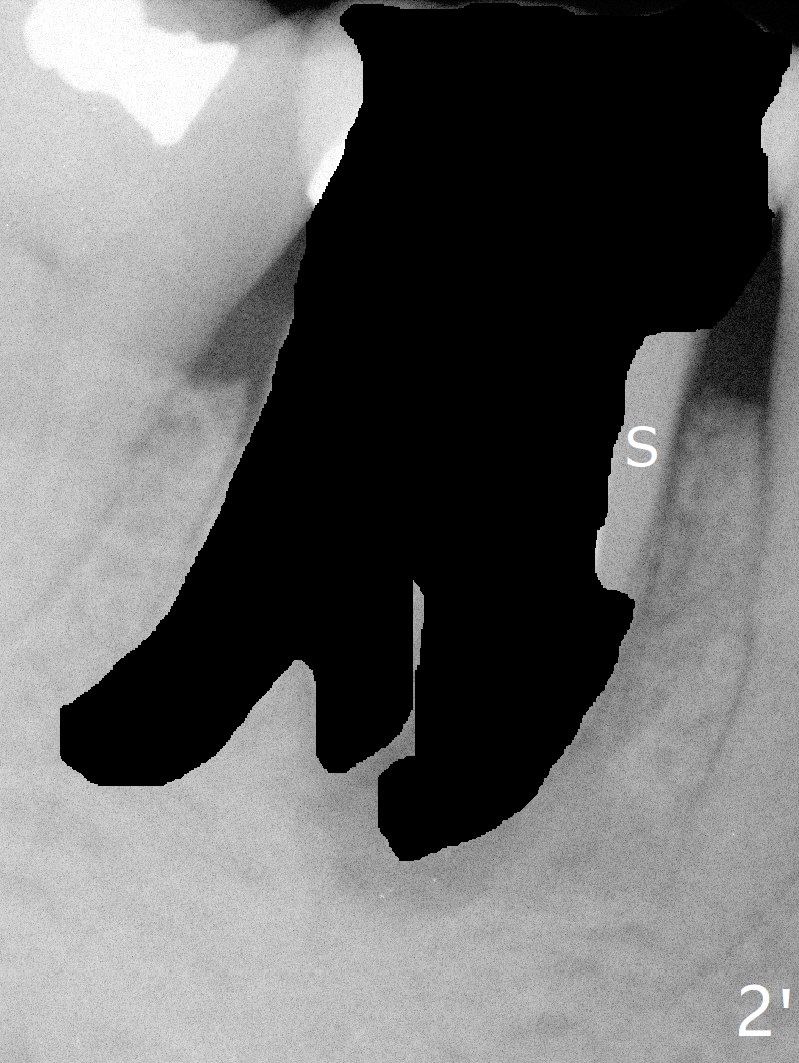

Mesial (or buccomesiolingual) socket shield may prevent the mesial bone loss and subsequent periimplantitis (Fig.2' S). Preop CT is a critical step in treatment planning.